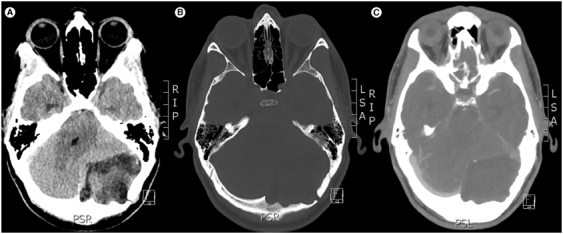

表皮样囊肿并不常见,在所有颅内肿瘤中占比不到 1%。其中,后窝巨大蝶鞍内表皮样囊肿(即超过5厘米的囊肿)更为罕见。在此,我们报告了对一名累及枕骨的 7 厘米后窝表皮样囊肿的完全切除,患者是一名 32 岁女性,头痛和眩晕由急性转为慢性加重。包括囊壁在内的完整切除对于防止复发和恶变至关重要。我们报告了迄今为止第一篇系统性综述,评估了 25 例后窝巨大表皮样囊肿病例,讨论了其表现、临床和影像学特征以及明确的治疗策略,为有限的现有数据增添了新的内容。

Epidermoid cysts are uncommon accounting for less than 1% of all intracranial tumors. Among them, giant intradiploic epidermoid cysts of the posterior fossa i.e. those exceeding 5 cm are an even rarer entity. Here we report on the complete resection of a 7 cm posterior fossa epidermoid cyst involving the occipital bone in a 32-year-old female presenting with an acute on chronic exacerbation of headaches and vertigo. Complete resection including the cyst wall is crucial in preventing recurrence and malignant transformation. We add to limited existing data by reporting on the first systematic review to date assessing 25 cases of giant epidermoid cysts of the posterior fossa to discuss presentation, clinical and radiographic features and definitive management strategies.